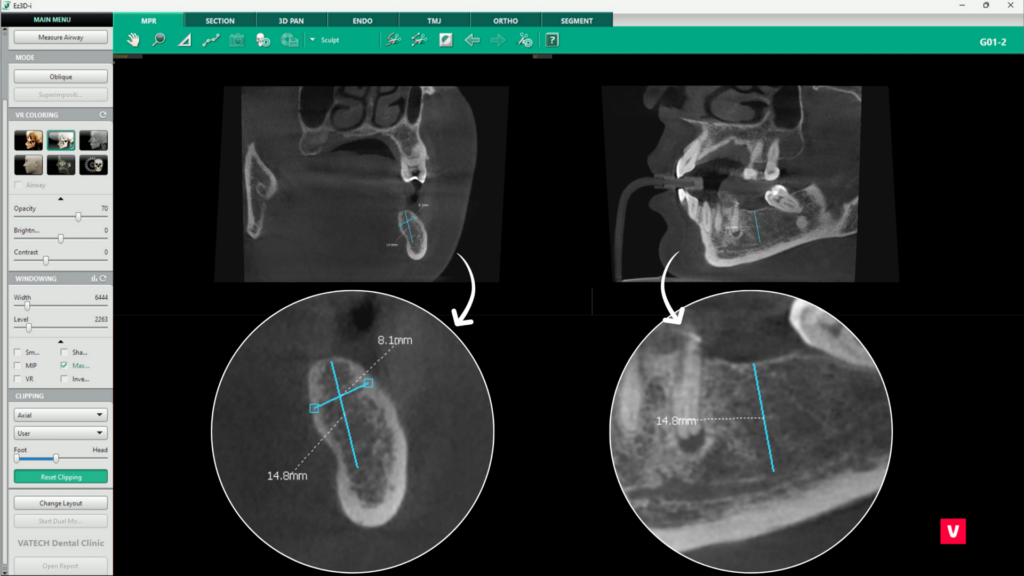

O evaluare corectă a densității osoase este esențială pentru succesul unui implant dentar. Deși am discutat în acest articolul despre numeroasele instrumentele dedicate analizării densității osoase, acest instrument specific oferă o verificare finală a compatibilității implantului cu osul în care urmează să fie plasat.

Disponibil în tab-ul 3D Pan, instrumentul poate fi activat prin selectarea opțiunii „Change Layout” din colțul stâng inferior al ecranului și alegerea unei configurații care include fereastra „Implant Bone Density”.

După selectarea implantului dorit printr-un click stânga, software-ul va genera automat un model grafic al acestuia, suprapus cu o reprezentare coloristică a densității osoase, conform scalei D1 – D5. Această reprezentare vizuală permite medicului să evalueze în detaliu structura osoasă din jurul implantului, identificând eventualele zone cu densitate scăzută care ar putea necesita proceduri suplimentare, cum ar fi augmentarea osoasă. Modelul poate fi rotit și analizat din orice unghi, oferind o perspectivă completă asupra viabilității implantului.